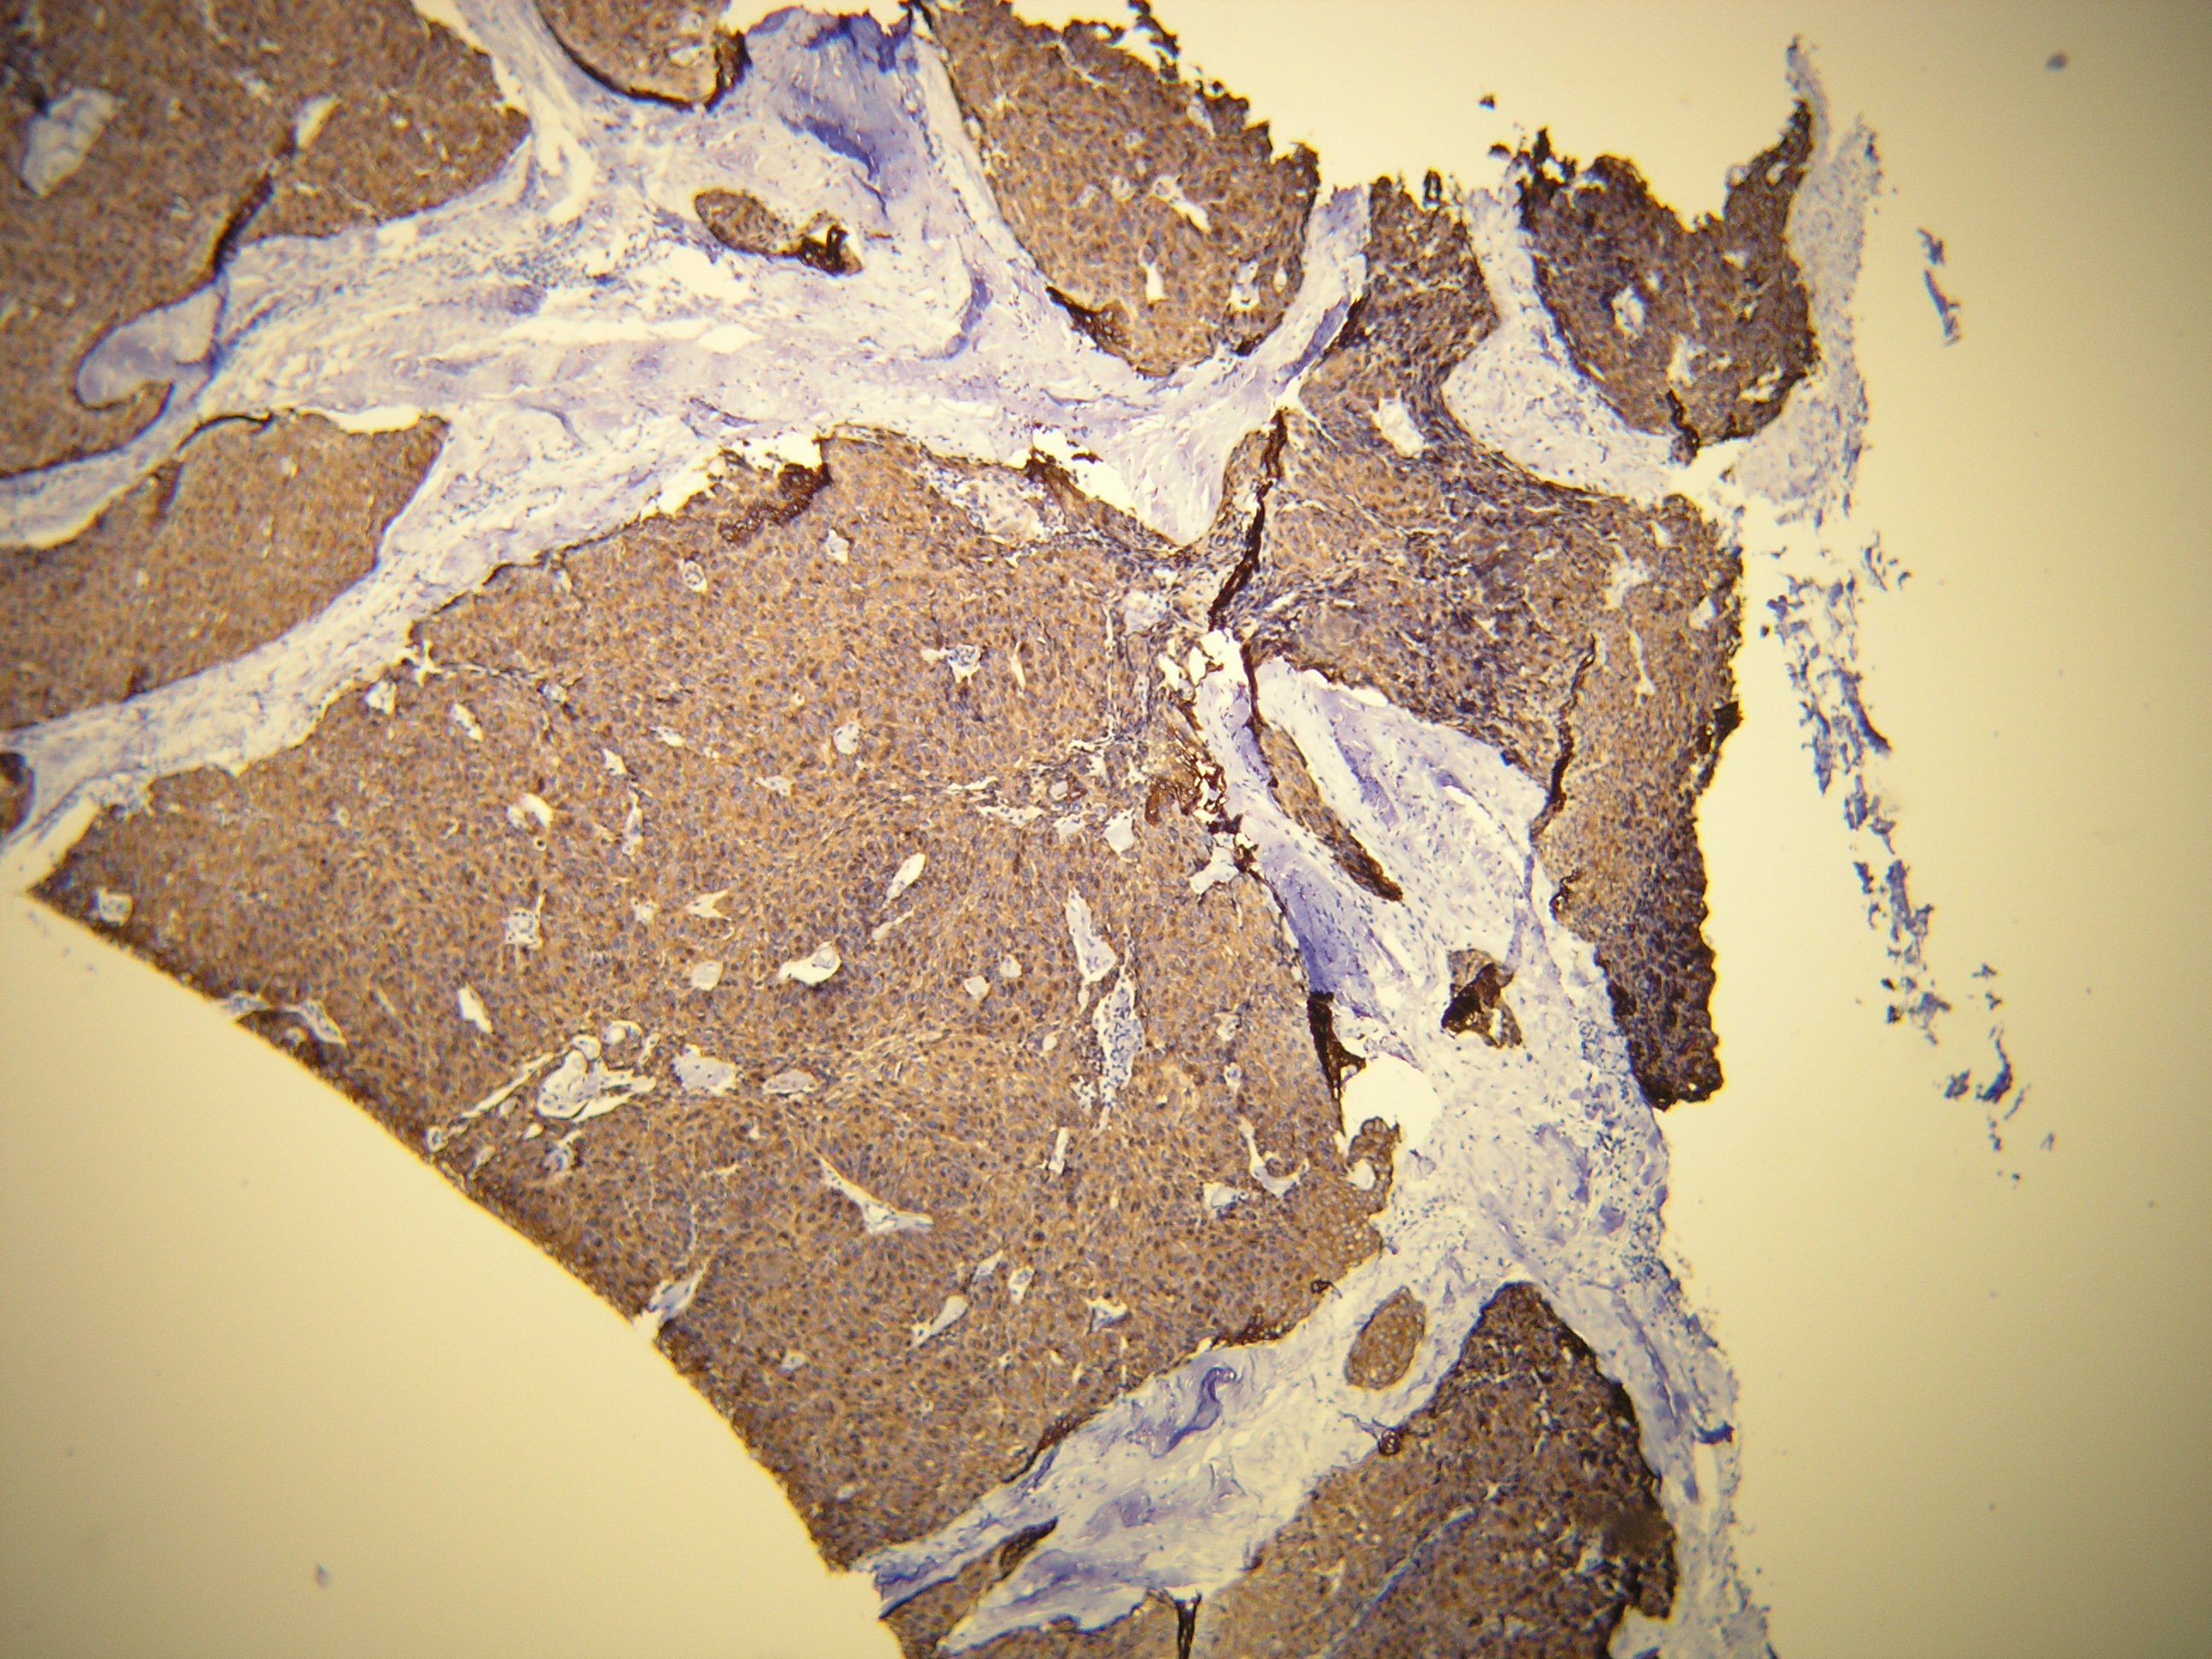

Anti-Cytokeratin 19

Peptid derivovaný z C-konca ľudského cytokeratin 19 proteínu. Protilátka rozpoznáva epitop umiestnený medzi Gly386 - Val399.

IHC-P, riedenie 1:100

db103a db103b